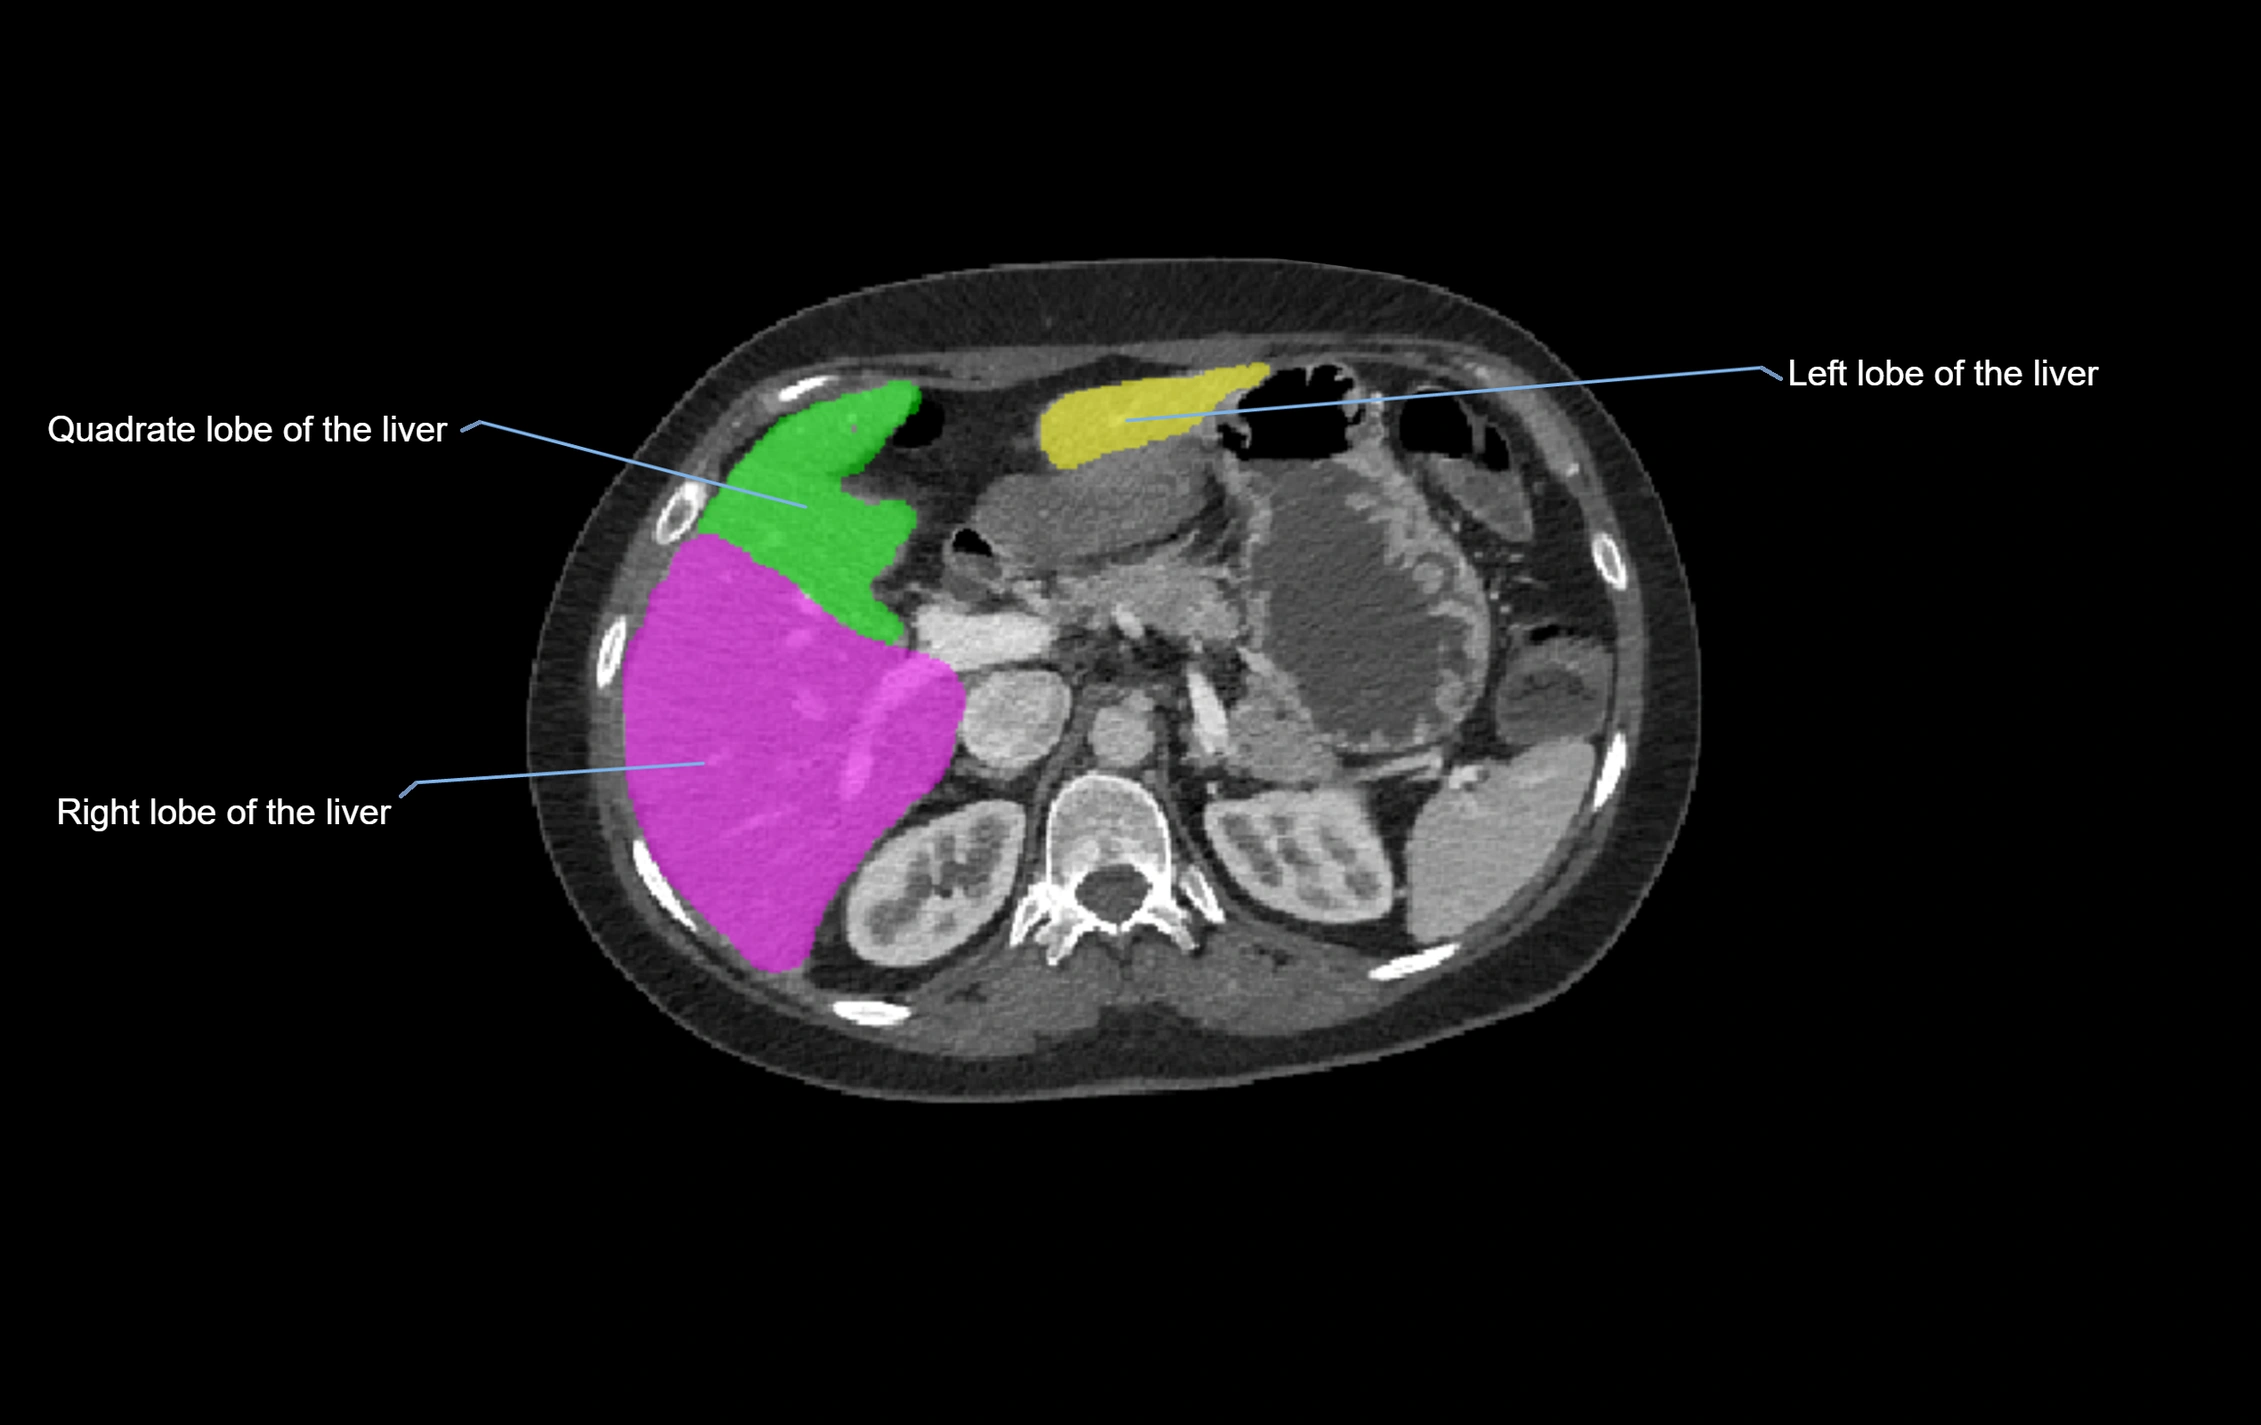

MRI image

image